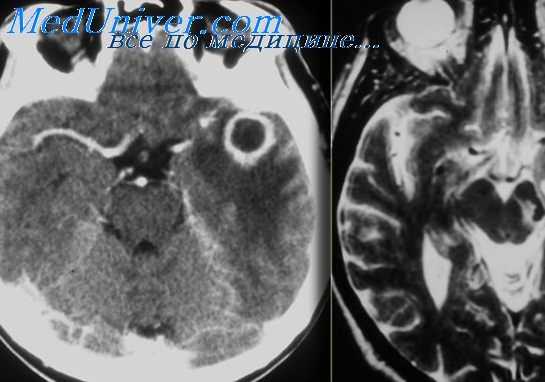

Абсцесс левого полушария мозжечка, выявленный при магнитно-резонансной томографии головного мозга в T1 C+ режиме на аксиальном срезе.

Абсцесс левого полушария мозжечка, выявленный при магнитно-резонансной томографии головного мозга в T2 режиме на аксиальном срезе.